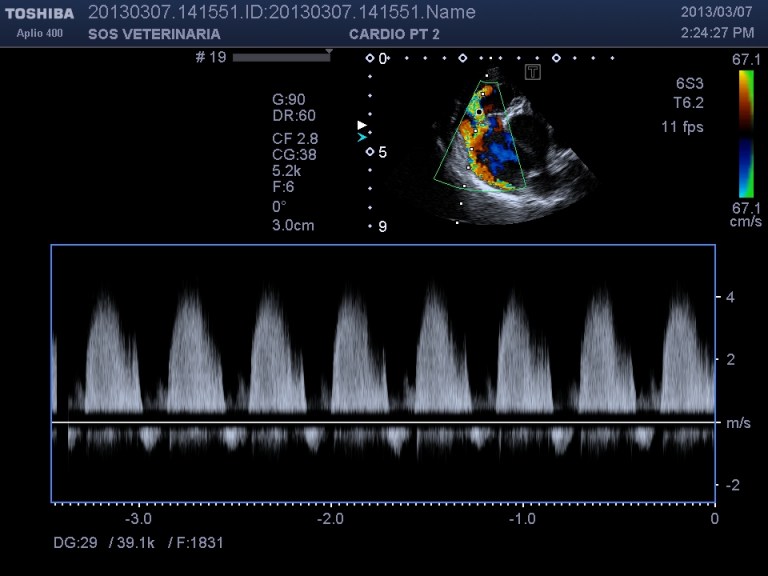

Ecco i filmati piu’ significativi osservare il flusso laminare che scorre parallelo alla parete laterale dell’arteria polmonare non piu’ continuo ma annullato in sistole dalla gittata in polmonare ,nel terzo filmato si vede l’ampolla del dotto